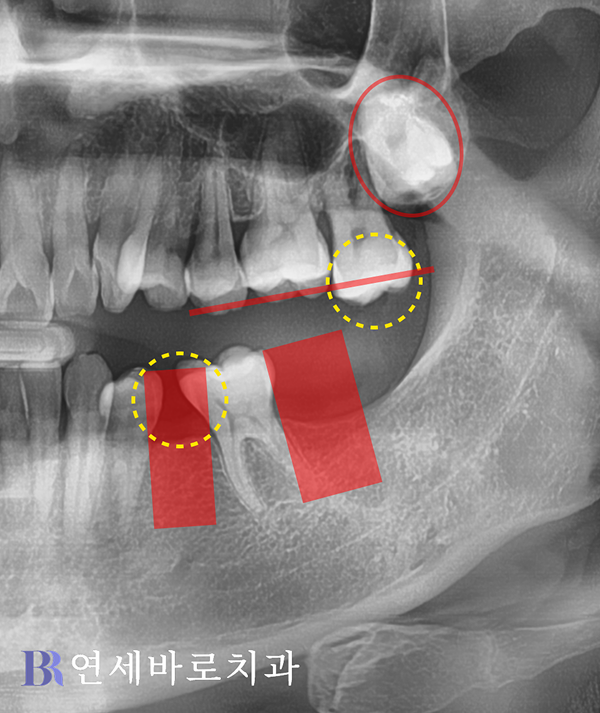

우선 제1대구치가 한쪽으로

기울어진 상태였는데요.

그러면서 제2소구치 부분에

매식체가 들어갈 공간이

상당 부분 소실되었습니다.

그래서 임플란트를 심으려면

그만큼 다른 자연치아를

삭제할 수 밖에 없었습니다.

게다가 사랑니 때문에 밀려

윗니 1개가 내려왔는데,

정상적인 교합을 완성하려면

영구치를 희생시키면서

높이를 맞춰주어야 했습니다.

환자분께 이점을 설명하고

부분교정으로 치아의 위치를

적절하게 조정하는 것이

어떻겠냐고 권해드렸습니다.